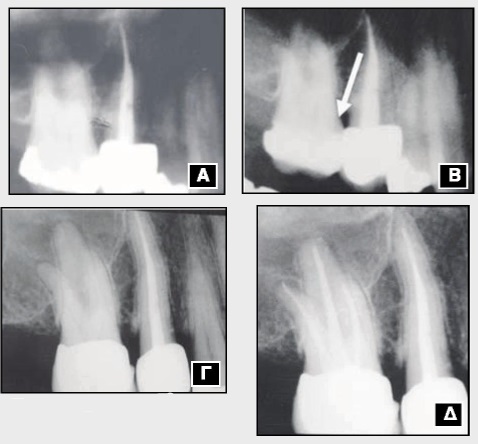

Εικ. 4: Αποκάλυψη πολφού (βέλος), έπειτα από τρόχισμα, σε δόντι που προορίζεται να γίνει στήριγμα προσθετικής αποκατάστασης. Η περίπτωση αποτελεί ένδειξη για ενδοδοντική θεραπεία.

Α. Εικόνα από πανοραμικό ακτινογράφημα (1997) όπου φαίνεται η ήδη υπάρχουσα έμφραξη αμαλγάματος στον 16.

Β. Εικόνα από πανοραμικό ακτινογράφημα (2001) όπου, μετά την αντικατάσταση της πρώτης έμφραξης, παρατηρείται δευτερογενής τερηδόνα στην αυχενική μοίρα της εγγύς επιφάνειας (βέλος).

Γ. Τοποθέτηση στεφάνης (2002).

Δ. Έξι μήνες μετά την τοποθέτηση της στεφάνης (2002) εκδηλώθηκαν συμπτώματα πολφίτιδας που οδήγησαν στην τέλεση της ενδοδοντικής θεραπείας.

Αναφέρθηκε προηγουμένως ότι ο πολφός των δοντιών αντιδρά στην παρουσία της χρόνιας τερηδόνας με την παραγωγή της αντιδραστικής οδοντίνης μέσα στον μυλικό θάλαμο. Η ίδια αντίδραση εμφανίζεται και μετά την παρασκευή της κοιλότητας προς αποκατάσταση ακόμα και σε περιπτώσεις με αβαθείς μασητικές εμφράξεις. Γενικότερα όμως, η αντιδραστική οδοντίνη παράγεται μετά την εφαρμογή ερεθιστικού παράγοντα στην οδοντίνη π.χ. τροχισμού, υλικών κ.ά. Το τελικό αποτέλεσμα όλων αυτών των διεργασιών, εφόσον ο πολφός διατηρείται ζωντανός, είναι η σμίκρυνση του μυλικού θαλάμου εις βάρος του πολφικού ιστού, γεγονός που έχει σαν συνέπεια τη μείωση των κυτταρικών και αγγειακών του στοιχείων. Τούτο, πιθανόν, να προκαλέσει τη μείωση της άμυνας του πολφού, έτσι ώστε να αντέχει λιγότερο σε νέους ερεθισμούς, ειδικά σε άτομα της τρίτης ηλικίας.Εικ. 5: Πολλαπλές οδοντιατρικές πράξεις σε ένα δόντι, που οδηγούν στη νόσο του πολφού.